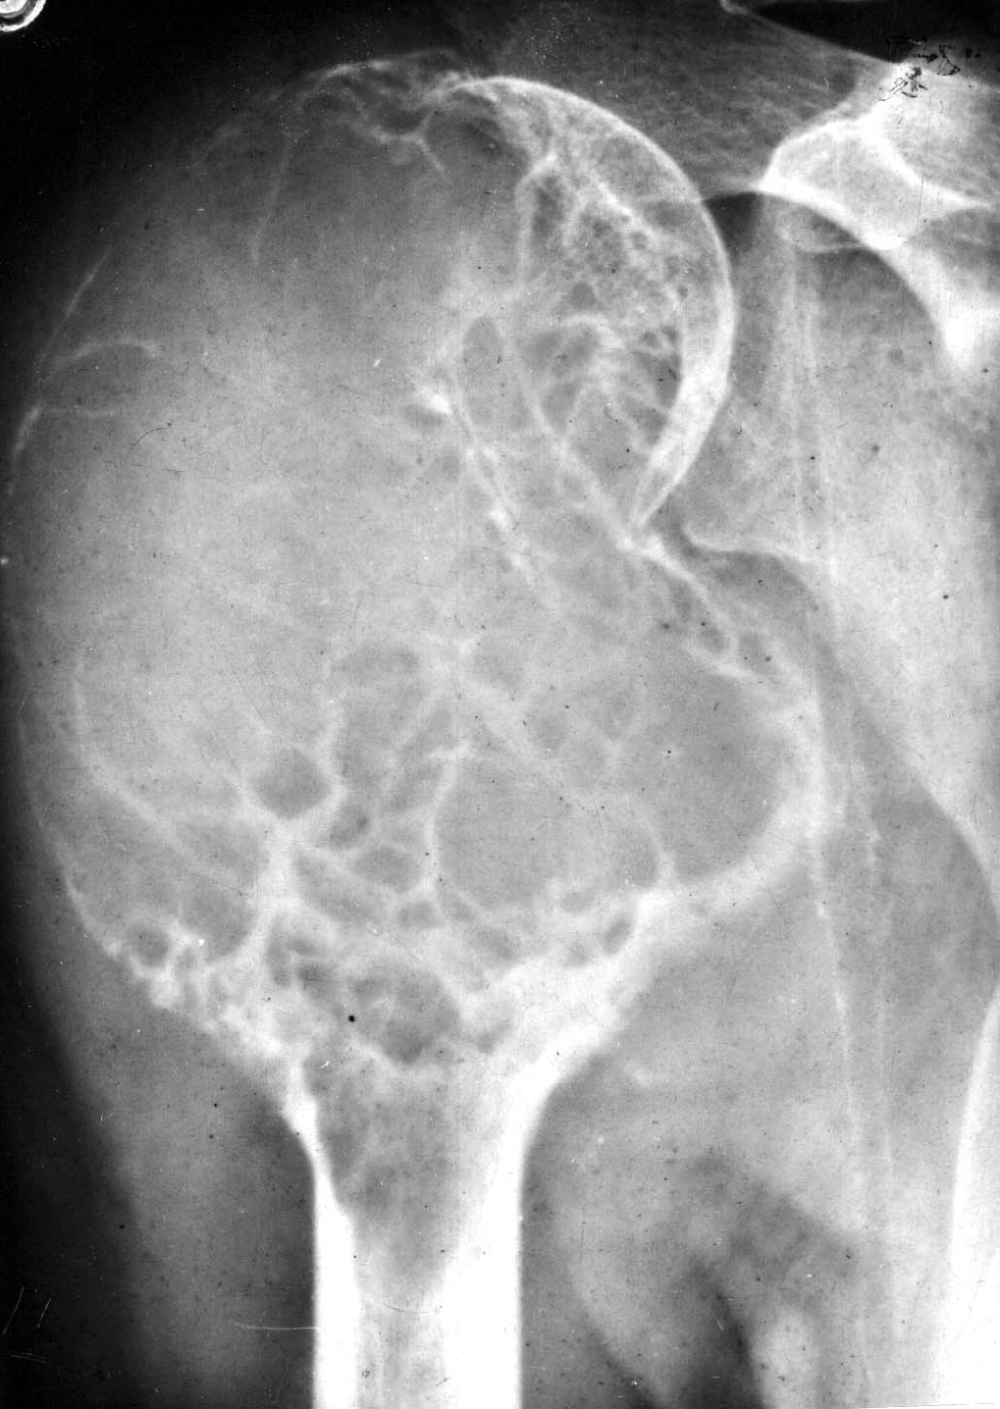

▌膨胀性破坏

膨胀性破坏是地图样破坏的特殊形式,影像学表现为骨质破坏区骨膨胀,周围可见不同程度扩张的骨壳(图 5、图 6、图 7、图 8)。膨胀性破坏是由于肿瘤从骨皮质内面破坏,骨外膜增生形成新生骨造成膨胀的。引起膨胀性破坏见于大多数良性肿瘤和肿瘤样病变如单纯性骨囊肿,动脉瘤样骨囊肿、内生软骨瘤和软骨粘液纤维瘤等,少数也可见于恶性肿瘤如转移瘤、骨髓瘤等。

图 6.膨胀性破坏:骨巨细胞瘤